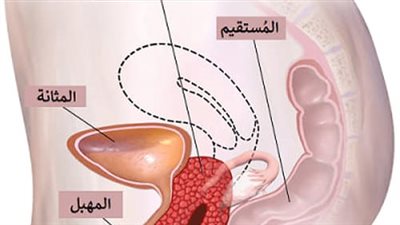

ولمن يرغب في معرفة إجابة سؤال ما الفرق بين التهاب الحوض واحتقان الحوض؟، يذكر الدكتور راني نذير الحبش، أن التهاب الحوض عبارة عن عدوى تصيب الأعضاء التناسلية للمرأة، منوهًا بأنه في معظم الحالات يكون أحد المضاعفات التي تنجم عن الأمراض المنقولة جنسيًا، ومنها: الكلاميديا والسيلان، فضلًا عن أن العدوى الأخرى التي لا تنتقل عن طريق الاتصال الجنسي قد تتسبب في حدوث الإصابة بهذا المرض.

ولكن مُتلازمة الاحتقان الحوضي تكون عبارة عن ألم مزمن بالجزء السفلي من البطن أى الحوض ينتج عن تجمُّع الدَّم بأوردة الحوض التي توسَّعت وأصبحت مفتولة.

كما قد يكون لدى النساء أيضًا دوالي وريدية بالأرداف، أو الفخذين، أو المهبل، أو الفرج.